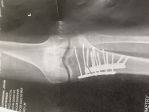

Bad is relative i suppose biggrin

Attachments

My God, John, you could open up a hardware store with all of those metal parts!